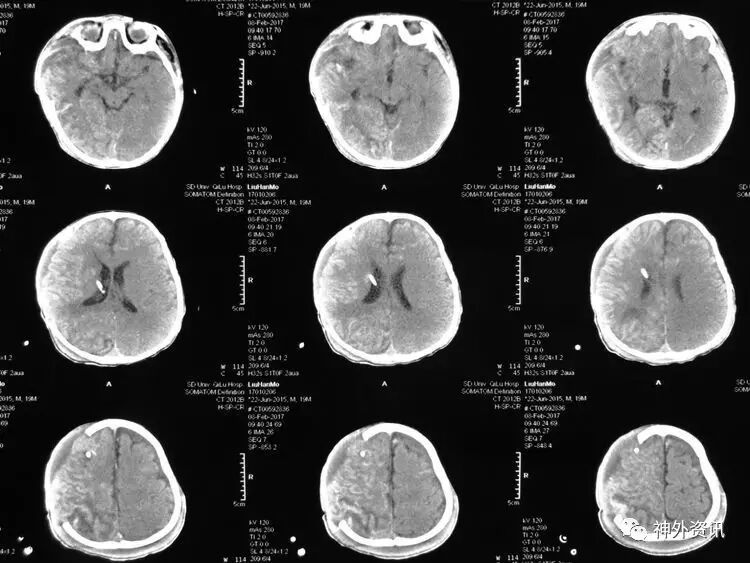

2017.2.1:术后2天复查颅脑CT,结果示中线居中,右侧半球低密度并SAH,左侧半球未见明显异常,左侧脑沟可见显示,双肺少量炎症,不能放松警惕,继续同前治疗。

2017.2.4:术后5天复查颅脑CT,结果示中线居中,左侧半球及环池显示清晰,右侧半球脑沟显示欠清晰,脑组织低密度较前有所好转,继续同前治疗。已加用预消化肠内营养液及促进胃肠动力药物。

2017.2.6:术后7天,复查颅脑CT示情况较前进一步好转,逐步撤掉冰毯,缓慢自然复温。

2017.2.8:术后9天,复查颅脑及胸部CT,结果显示双侧脑沟脑回及环池显示清晰。颅压控制,拔除引流管探头,头部敷料稍加压包扎,此时已更替力月西为丙泊酚,停用呼吸机。